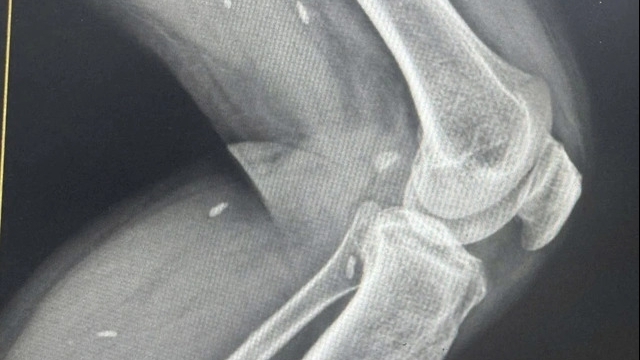

Sau khi hội chẩn, các bác sỹ chẩn đoán ông Dore Perunovic có khả năng bị tai biến với các triệu chứng mất cảm giác toàn thân, mắt trái không nhắm được; đau cột sống, huyết áp tăng cao; bệnh nhân cần sớm được tiếp cận y tế và đưa về bờ khẩn cấp để điều trị.